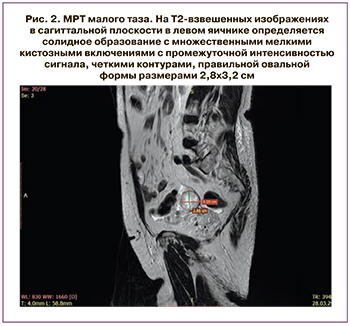

Пациентка Л., 80 лет, проходила комплексное обследование и лечение в ГБУЗ «Московский клинический научный центр имени А.С. Логинова» (МКНЦ). В 2018 г. в клинике женского здоровья МКНЦ имени А.С. Логинова у пациентки диагностирован рак правой молочной железы pT2(m)N0M0, IIA стадия, люминальный тип B, Her-2-негативный. В октябре 2018 г. выполнено хирургическое лечение в объеме радикальной мастэктомии справа по Маддену и проведена последующая гормональная терапия с использованием ингибитора ароматаз анастрозола. Гинекологом по данным ультразвукового исследования диагностирован гиперпластический процесс эндометрия, кистозное образование левого яичника. Учитывая высокий риск злокачественной патологии, было выполнено комплексное обследование. На первом этапе произведены гистероскопия, раздельное выскабливание цервикального канала и полости матки. По данным морфологического исследования: железисто-фиброзный полип эндометрия без атипии. Выполнена МРТ органов малого таза, при которой подтвердилось солидное образование левого яичника диаметром 33 мм, накапливающее контрастный препарат (рис. 2).

Редкая встречаемость данных опухолей требует тщательного подхода к диагностическому поиску. Необходимо проводить дифференциальную диагностику с рядом заболеваний, имеющих сходные клинико-морфологические характеристики, в частности с опухолью желточного мешка, сертолиформной эндометриоидной аденокарциномой, злокачественной смешанной мезодермальной опухолью [8]. Для диагностики опухолей Сертоли–Лейдига показано проведение гормонального исследования: определение сывороточного уровня тестостерона, дегидроэпиандростерона, дегидроэпиандростерон-сульфата, 17-гидроксипрогестерона, кортизола [8]. Исследование онкомаркеров показано при любых опухолях яичников; для диагностики неэпителиальных новообразований целесообразно применять СА-125, Не4, ингибин В, α-фетопротеин, β-хорионический гонадотропин человека [8, 39]. Ультразвуковое исследование, компьютерная томография и магнитно-резонансная томография (МРТ) включены в спектр инструментальных методов обследования больных опухолями стромы и/или полового тяжа [8, 39]. Отличительными особенностями МРТ опухолей Сертоли–Лейдига являются такие характеристики, как солидная структура образований, наличие ровных четких контуров, возможное наличие кистозной трансформации, накопление контрастного препарата мягкотканным компонентом [39].